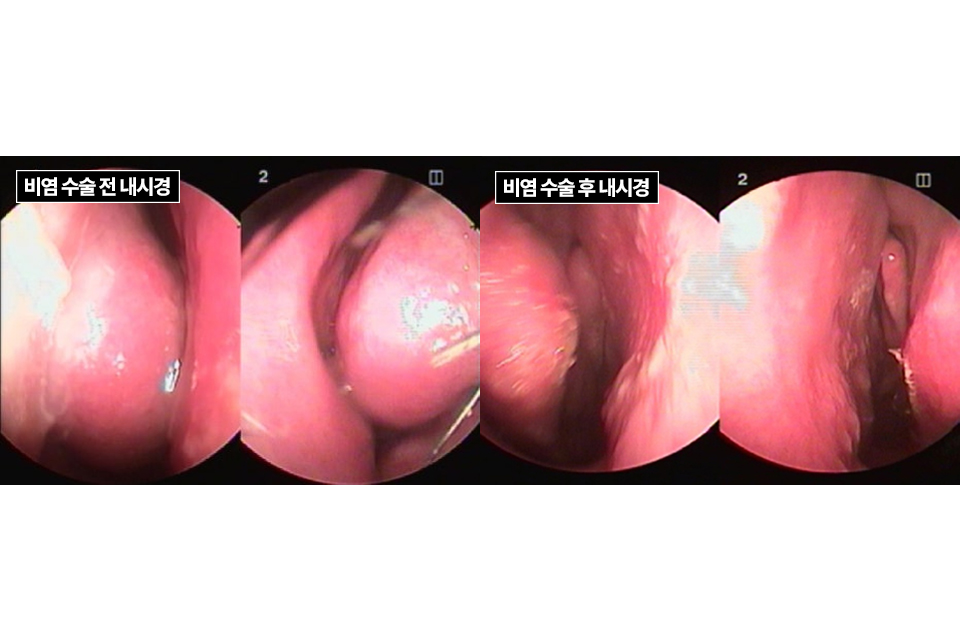

실제 비중격만곡증 수술 환자의 수술 과정을 통해 살펴보겠습니다.